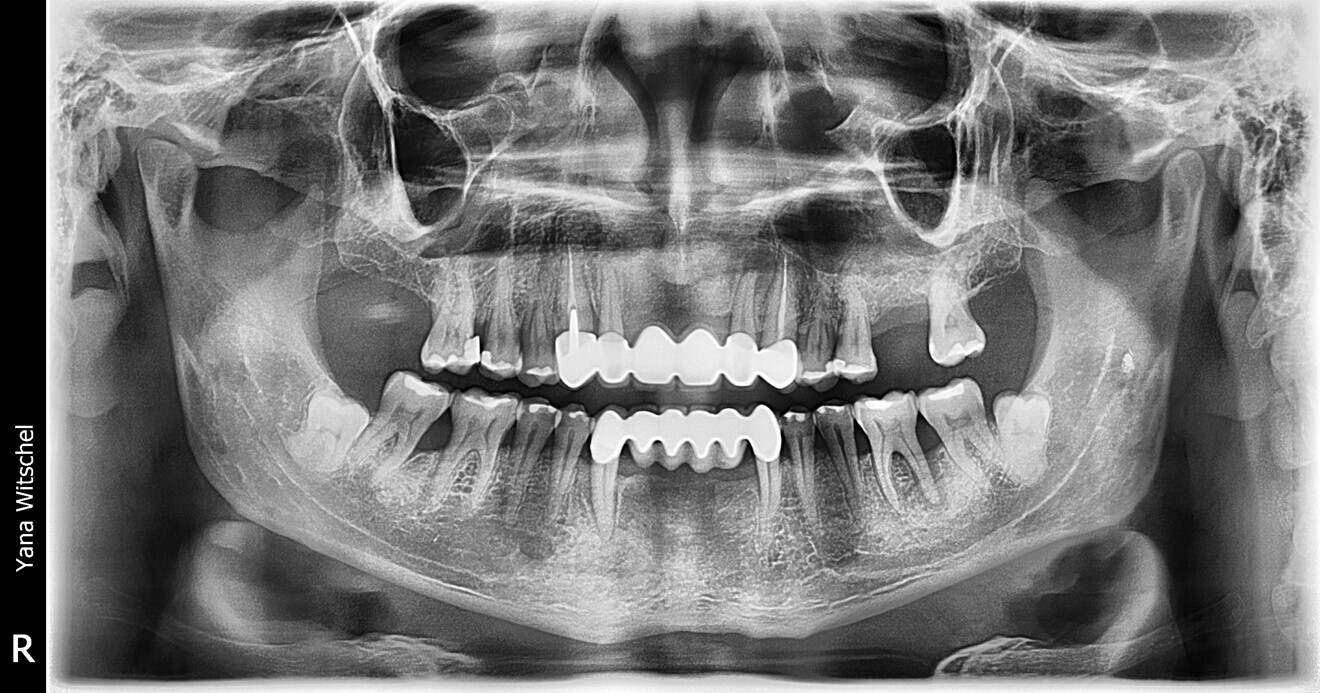

Fig. 1: Panoramic radiograph before treatment. (All images: Yana Witschel)

A panoramic radiograph showed no radio-opacity in the maxillary sinus and no changes to the temporomandibular joints. There were radiopacities suggestive of fillings in several teeth. Horizontal bone loss of moderate extent (approximately 50%) was generally present, along with very pronounced vertical bone loss mesial to tooth #13, distal to tooth #36, mesial to tooth #33, distal to tooth #43, and mesial to and in the bifurcation of tooth #47 (Fig. 1).

The radiographic findings, including 50% horizontal bone loss and severe vertical bone loss around teeth #13, 36, 33, 43 and 47, along with attachment loss of up to 12 mm, considering the patient’s age, led to the diagnosis of generalised severe chronic periodontitis. Microbiological diagnostics were initiated on the basis of the periodontal findings, revealing a high bacterial load, especially of the A.a. complex (A. actinomycetemcomitans) and red complex (P. gingivalis).